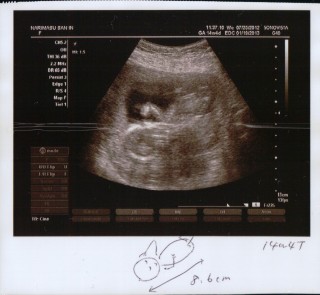

座高76.8mm。足や手を元気に動かしていて安心しました!また一ヶ月後が待ち遠しい!

8.6cm

CRL=69.9mm